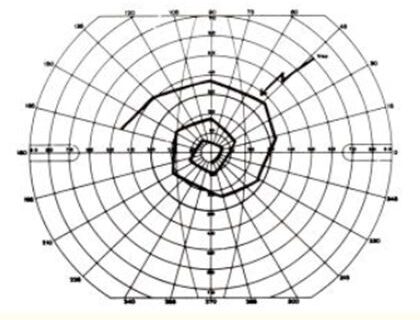

Αποκόλληση Αμφιβληστροειδούς on/off

Η προσβολή της ωχράς κηλίδας σε οφθαλμούς με αποκόλληση αμφιβληστροειδούς αποτελεί δυσμενή προγνωστικό παράγοντα για τη μετεγχειρητική λειτουργική αποκατάσταση ως προς την οπτική οξύτητα και όχι μόνο. Ωστόσο δεν πρέπει να παραβλέπεται το γεγονός πως η χρονική διάρκεια παραμονής υποαμφιβληστροειδικού υγρού στην περιοχή της ωχράς έχει καθοριστική σημασία, καθώς αποκατάσταση εντός 72 ωρών έχει αποδειχθεί…